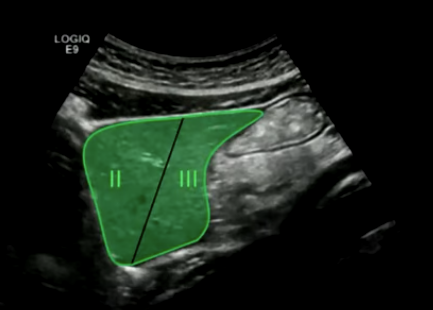

Left Hemi Liver:

Segments two, three, and four. These segments are supplied by the left hepatic artery and portal vein branch.

Separates segments two and three from four. It is a peritoneal fold that extends from the anterior abdominal wall to the liver.

Falciform ligament separates segments two and three from segment four. This is a key landmark for dividing the left lobe.

Sagittal

Probe placement: The probe is typically placed in the intercostal spaces to obtain sagittal views of the liver.